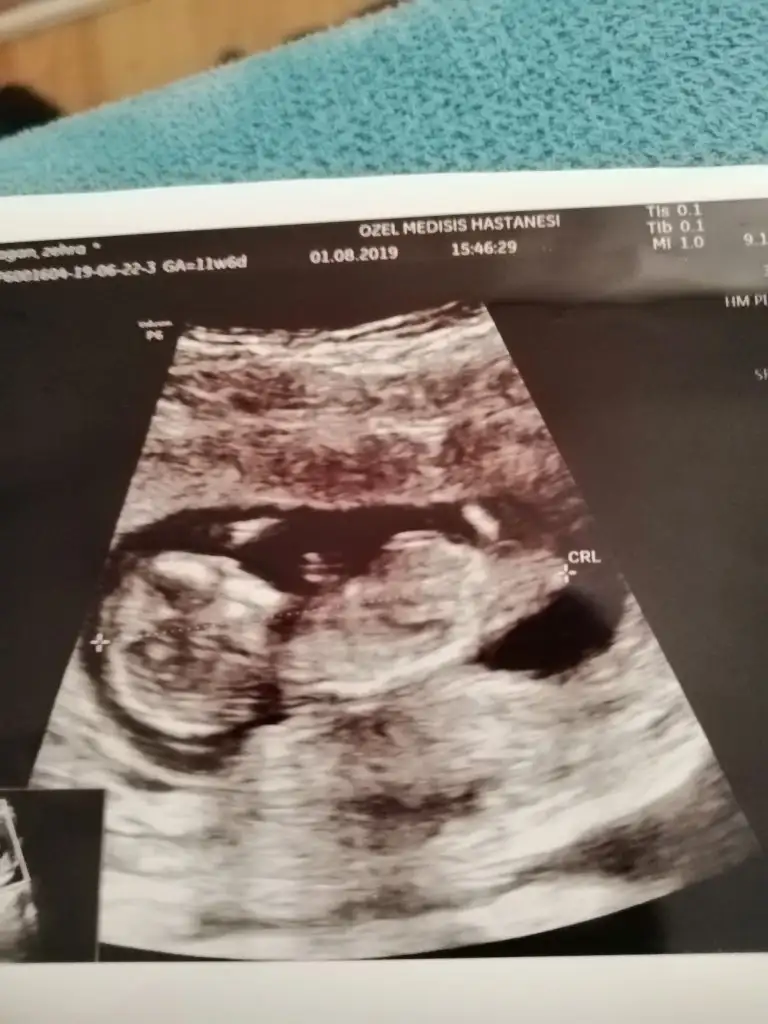

Kızlaar bende çok merak ediyorum geçen hafta 11+5 ken bunlar İpucu veriyormu sizce cinsiyet nedir?

Eki Görüntüle 2294671

Siz erkek istiyordunuz galiba.nub çizgisine ve kafa yapısına göre yorum yapıyorum.cinsiyet oluşmadan önce nub çizgisi oluşur.bu çizgi paralelse kız,dik ise erkek demektir.sizin bebeğinizin nub çizgisi bariz paralel.kafa yapısı da oval.erkeklerin kafa yapısı daha yuvarlak olur. Doktor kesin erkek dedi mi size? Buda cinsel organı diye gösterdi mi? Kaç haftalıksınız şuan?Doktor organını bile gösterdi bu çıkıntı olabilir diye yine de cevabınız için teşekkür ederim merakımdan soruyorum yanlış anlamayın neye göre Tahminde bulunuyorsunuz mesela son resim tam olarak neyi gösteriyor hiçbirşey anlamadım

Evet gönlümden geçen erkek Bi tane kızım var çok ta sevinmiştim siz şimdi kesin kız deyince moralim bozuldu biraz. Şu an sat a göre 11 hafta 6 gün usg ye göre 12 hafta 6 gün. Doktor erkeğe çok benziyor çıkıntısı burada diyerek gösterdi kesin erkek demedi yüzde 80 erkek dedi ama bazen kızlarda da bu çıkıntı oluyor dedi. Hatta bu Nub teorisinden de bahsettim belli olmaz bazen dik bazen paralel bile olabilir dediSiz erkek istiyordunuz galiba.nub çizgisine ve kafa yapısına göre yorum yapıyorum.cinsiyet oluşmadan önce nub çizgisi oluşur.bu çizgi paralelse kız,dik ise erkek demektir.sizin bebeğinizin nub çizgisi bariz paralel.kafa yapısı da oval.erkeklerin kafa yapısı daha yuvarlak olur. Doktor kesin erkek dedi mi size? Buda cinsel organı diye gösterdi mi? Kaç haftalıksınız şuan?